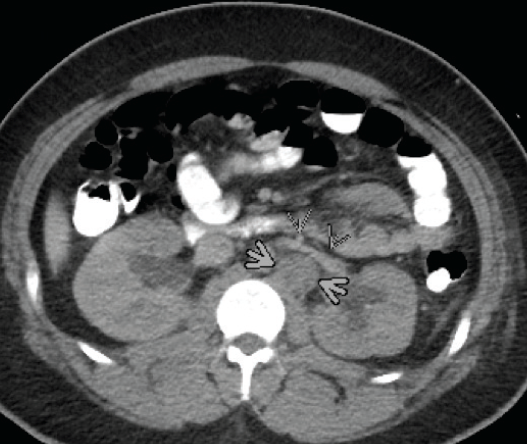

Erica Co-Reyes, MD; Ronen Zipkin, MD; Jodi Nagelberg, BA, MHA

A previously healthy 3-year-old girl presented to the emergency department (ED) with a 2-day history of bloody stools and abdominal pain.